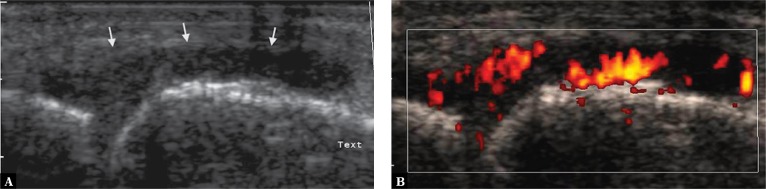

Color or power Doppler option should be used as the next step of the diagnostic workup. The presence of a vascular network within the lesion allows to differentiate inflammatory lesions and evaluate the inflammatory activity (Fig. 14), as well as identify abnormally healing lesions with a history of trauma or chronic mechanical overuse (Fig. 15 A)(8). Whenever the presence of such lesions is suspected, a sensitive Doppler option should be used.

Fig. 14.

Metacarpophalangeal joint: A. thickened joint capsule with hypoechoic edema of the synovium (arrows,) resembling fluid; B. power Doppler scan showed numerous vessels consistent with highly active inflammatory lesions (Grade 3 vascularity)

Fig. 15.

Enthesopathy at the proximal insertion of the patellar ligament, lesions with the history of overuse injury in A professional athlete: A. power Doppler option shows multiple vessels at the proximal insertion of the patellar ligament, consistent with abnormal healing with angiofibroblastic hyperplasia; B. vessels not visible when stronger pressure is applied with the transducer

Imaging blood vessels of the musculoskeletal system is aimed at identifying increased tissue vascularization (hyperemia) or any vascular pathologies, that is finding out whether blood vessels are visible, what is their number and location. It is necessary to try to visualize even the smallest vessels in the smallest structures, such as the nerves. Hence, searching for few, small vessels, the Doppler mode requires maximum gain at the level of small motion artifacts. The correct technique requires proper immobilization of the transducer without compressing the tissues (Fig. 15 B). Artifacts typically show as random color flashes; in the vicinity of larger vessels perivascular tissue pulsation may be detected.